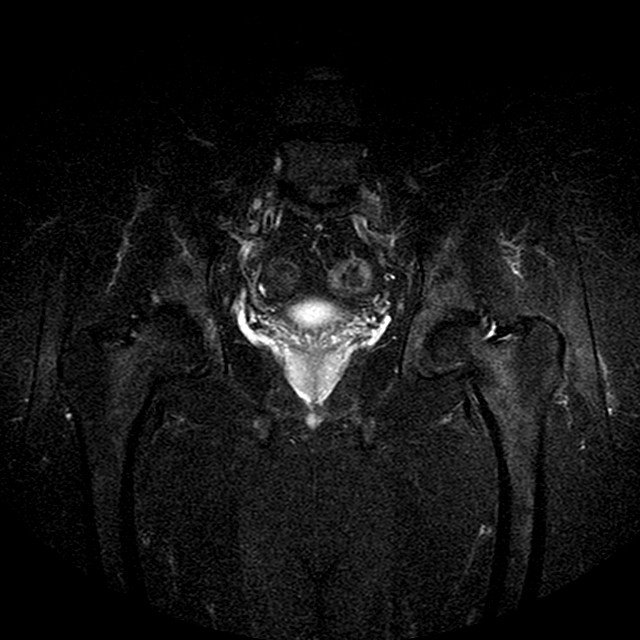

STIR

Evidenti e simmetriche alterazioni osteofitosiche in regione coxo femorale con riduzione delle rime articolari. Degenerazione completa del cercine glenoideo. Non attuali segni di versamento articolare. Non segni di edema osseo che escludono attuale algodistrofia od osteonecrosi. Lieve e simmetrica riduzione del trofismo della muscolatura glutea.